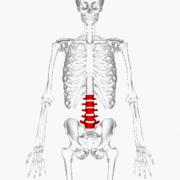

![]() Position of human lumbar vertebrae (shown in red). It consists of 5 bones, from top to down, L1, L2, L3, L4 and L5. | |

The lumbar vertebrae are, in human anatomy, the five vertebrae between the rib cage and the pelvis. They are the largest segments of the vertebral column and are characterized by the absence of the foramen transversarium within the transverse process (as it is only found in the cervical region), and by the absence of facets on the sides of the body (as only found in the thoracic region). They are designated L1 to L5, starting at the top. The lumbar vertebrae help support the weight of the body, and permit movement.